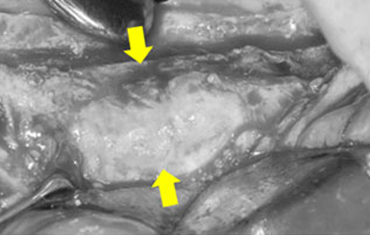

타 치과의 뼈 이식 후 골조직

램브란트치과 상인점 뼈이식 후 골조직

뼈의 폭은 좋으나 함몰 부위

함몰 부위에 국소적으로 적용하는 간단한 방법의 뼈이식 임플란트

잇몸뼈가 찰 때까지 기다릴 필요 없이 즉시 식립과 동시에 뼈이식